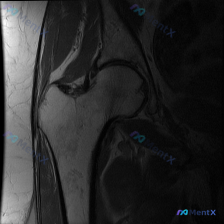

看到一个髋关节MRI病例,单幅冠状位T2加权像显示髋臼外上缘盂唇有局灶性高信号改变。正常情况下,盂唇在T2加权像上应该是低信号的。大家看看这个高信号更可能是盂唇撕裂还是退变?还需要补充哪些序列的图像来明确诊断?

看到一份髋关节MRI病例资料,原提问者提到“髋臼唇病变(Labral pathology)”。先放影像分析的核心发现: - 股骨头外上方承重区轮廓塌陷、变平,形态失真 - 股骨头内有特征性低信号带,将股骨头分为内侧正常区和外上侧异常区 - 软骨下骨板不连续,有“新月征”改变 - 关节间隙尚存,但有非...